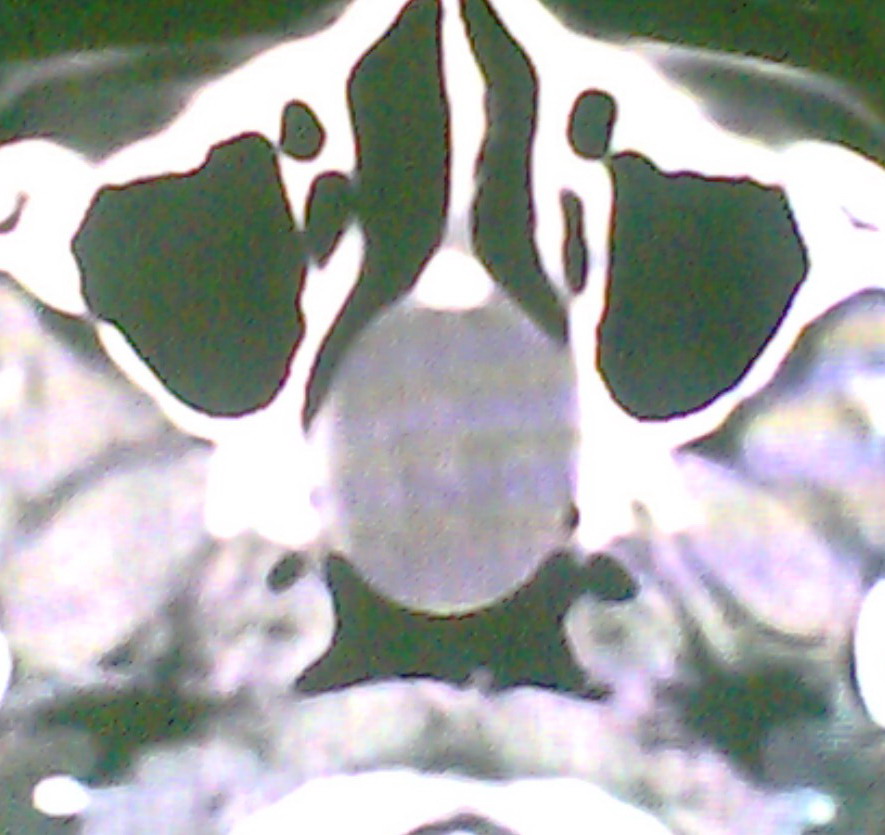

女、18岁,身高1.5左右,鼻塞、流涕数月,两侧瞳孔明显增大,曾与几年前去北京看眼,未发现病变。

考虑起源与蝶窦的粘液囊肿。

考虑脑膜脑脊液鼻内膨出

考虑起源于蝶窦的粘液囊肿突入鼻咽部。

\"几年前去北京看眼\"不知这句话有何玄机,支持考虑脑膜脑脊液鼻内膨出,膨出口在蝶鞍处

建议冠状面扫描,支持:脑膜鼻内膨出; 蝶窦粘液囊肿突入鼻腔可能性小。

在上级医院冠状位ct扫描后,诊断为:脑膜膨出,已住院准备手术。等待术后结果。